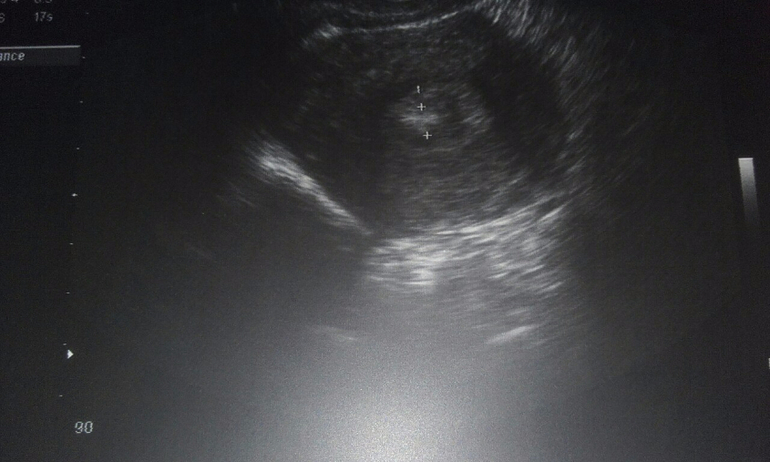

17 дц..Кто понимает по узи..

ФолликулометрияДевочки..Сходила утром на узи..О была..Но..Ставят полип эндометрия..Что это вообще..Хотя она не уверена в этом..

А вы на какой д.ц. делали УЗИ? Дело в том, что мне тоже ставили полип под ? на 25 д.ц.!!! На экране была точно такая же картинка!!! Она мне специально указала на это место! Но гинеколог сразу сказала, что возможно это просто эндометрий такой!!! Назначила повторное узи на 5 д.ц!!! Я очень переживала...но оказалось, что напрасно!!! все вышло во время менструации!!! Поэтому не паникуйте раньше времени!!! Обязательно сходите на контрольное УЗИ!!! Удачи!!! Не болейте!!!

Ааа...была О.показалось.что дф видно.по полиуретана не скажу.надо вроде на 5 дц смотреть.или на гистере

Да..Один ДФ лопнул..Она сказала еще один 23 мм уже..Я обалдела..Но..Она сказала что он может и не успеет..Так как М через неделю..Хотя..